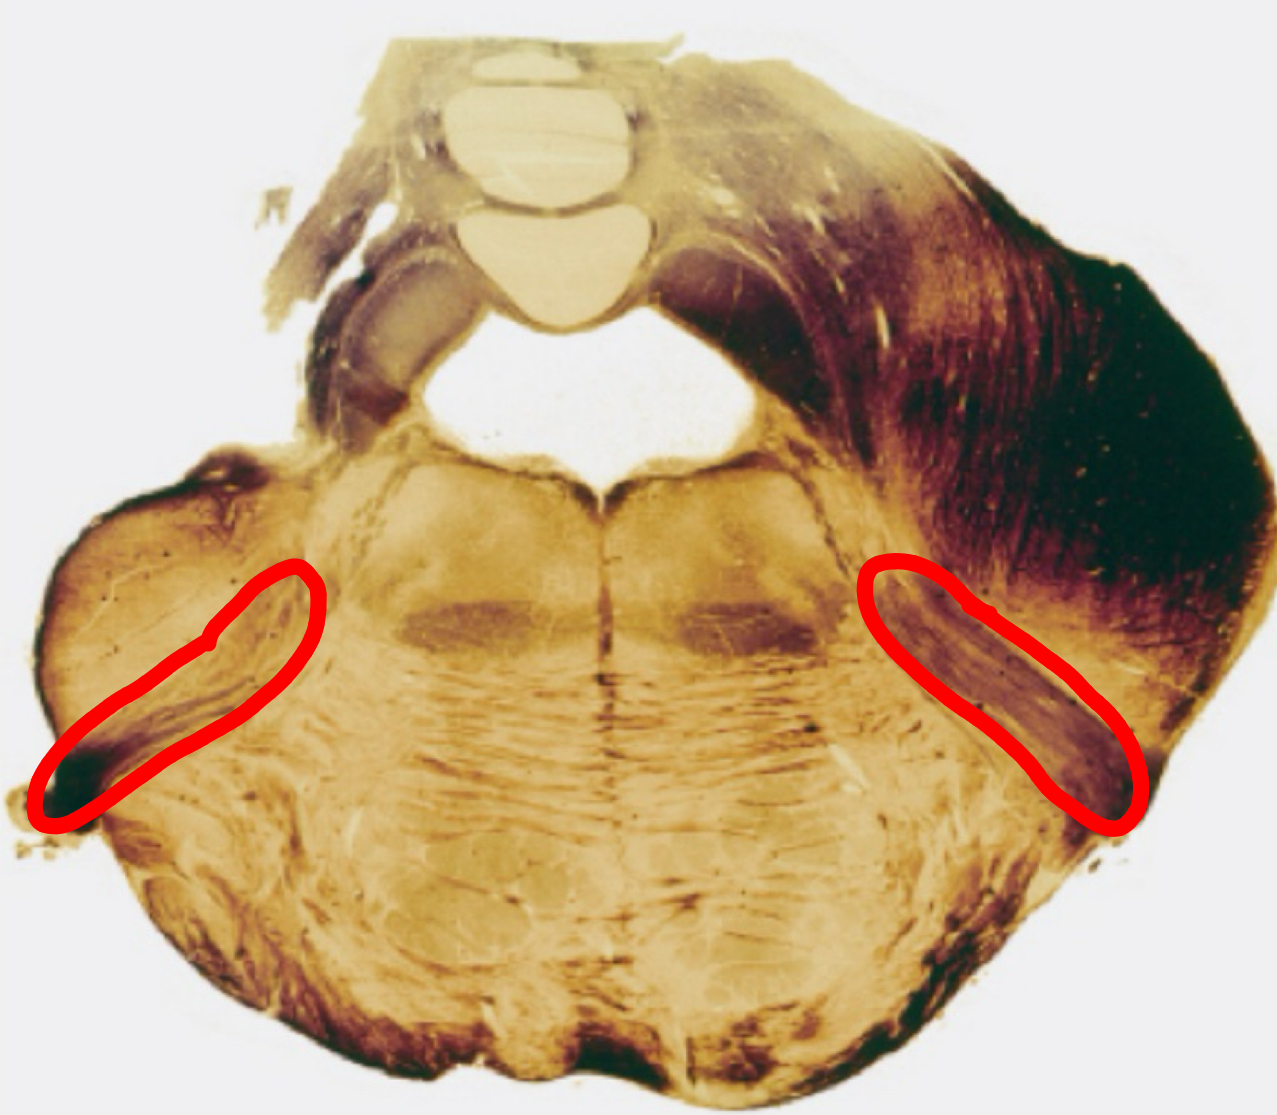

medial lemniscus rostral medulla

inferior cerebellar peduncle rostral medulla

inferior olivary complex rostral medulla

reticular formation rostral medulla

pyramidal tracts rostral medulla